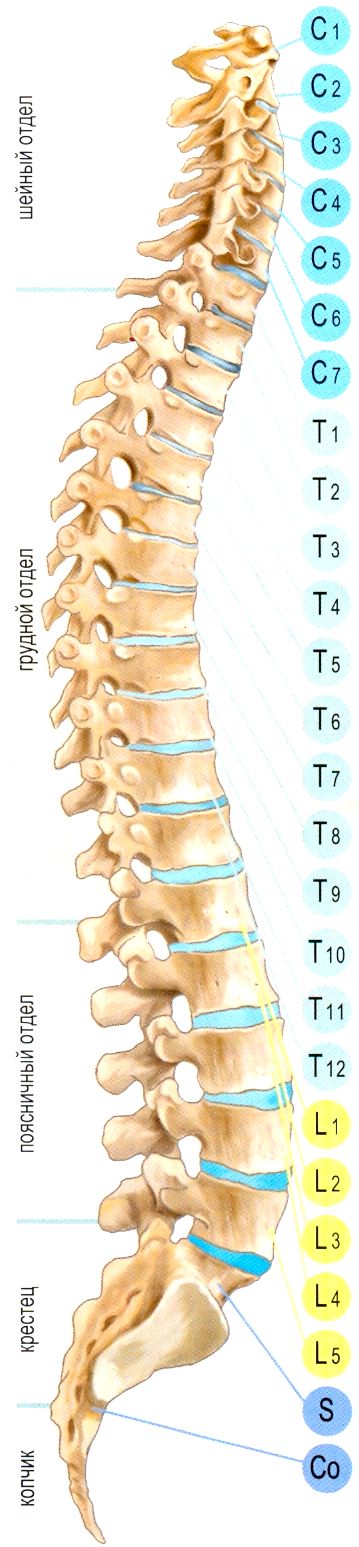

Позвонок Th10: анатомия и фото медицинских иллюстраций